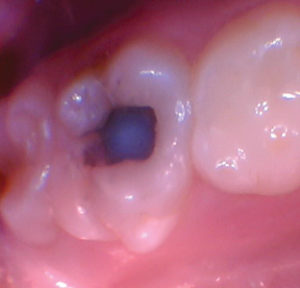

Figura 1 Vista preoperatoria del primer molar primario superior. |

Figura 2. La exposición pulpar se produjo al excavar la dentina infectada (la exposición pulpar no se capturó en la foto). |